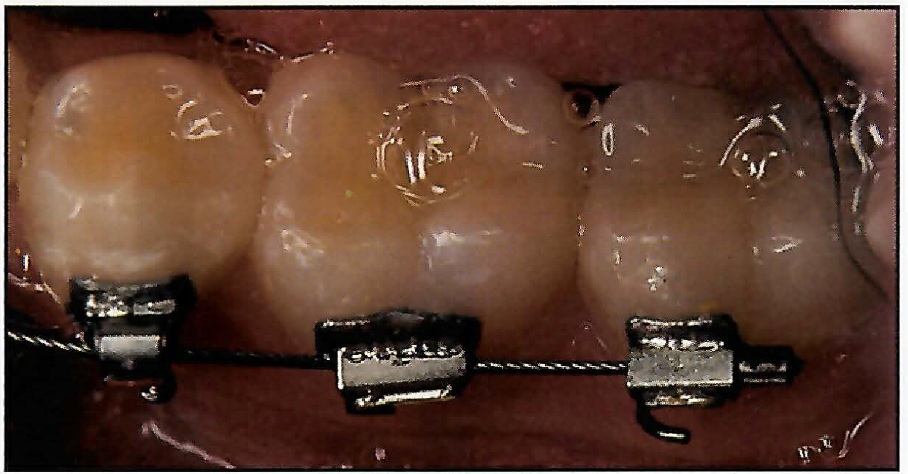

Supercable's unique construction and superelastic properties permit it to be gently engaged in even the most crowded cases without patient discomfort (Fig. 4).

Fig. 4 A. Placement of initial mandibular .01611 Supercable archwire. B. Segmented .01611 Supercable wire, seated in auxiliary slot of maxillary lateral and first bicuspid brackets, is flexible enough to be fully engaged in main archwire slot of palatally displaced cuspid.